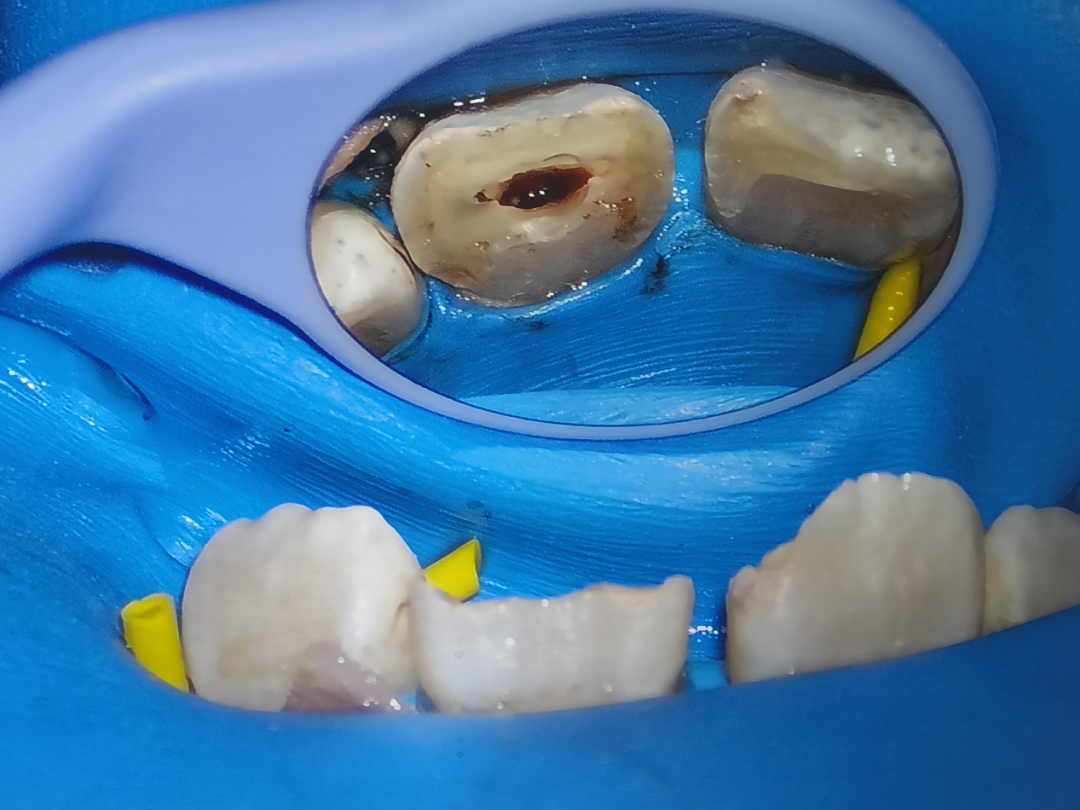

4.显微根管治疗

显微根管治疗是我科在牙体牙髓病领域的精尖技术,标志着牙髓治疗从传统经验迈向可视化精准化的新纪元。

传统治疗依赖手感与经验,而牙科手术显微镜将根管系统清晰呈现于眼前,使医生能清晰辨识钙化根管、遗漏根管及复杂变异,以彻底清除传统器械无法触及的感染组织。

凭借显微技术,显著提升了疑难病例(如根管内异物取出、根管壁穿孔修补等)的成功率,成功挽救了大量曾被判定“只能拔除”的患牙。在解除患者痛苦的同时,最大限度地保留了他们的天然牙,实现了“微创保真”的终极目标。